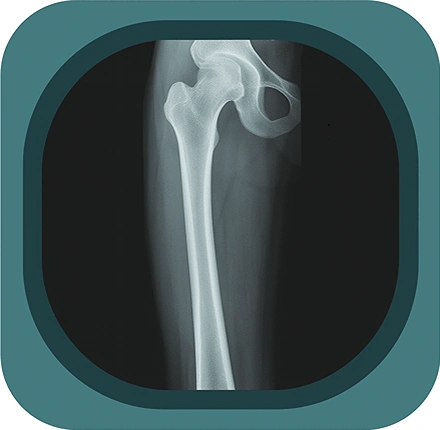

Explore high-quality X-ray anatomy from head to toe. Our database features carefully labelled images to visualize fine structuresโ€”perfect for radiologists, students, and surgeons.